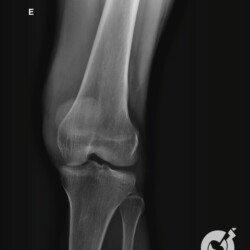

Fratura da patela com importante desvio e fratura cominutiva do 1/3 proximal da tíbia comprometendo a eminência intercondiliana.